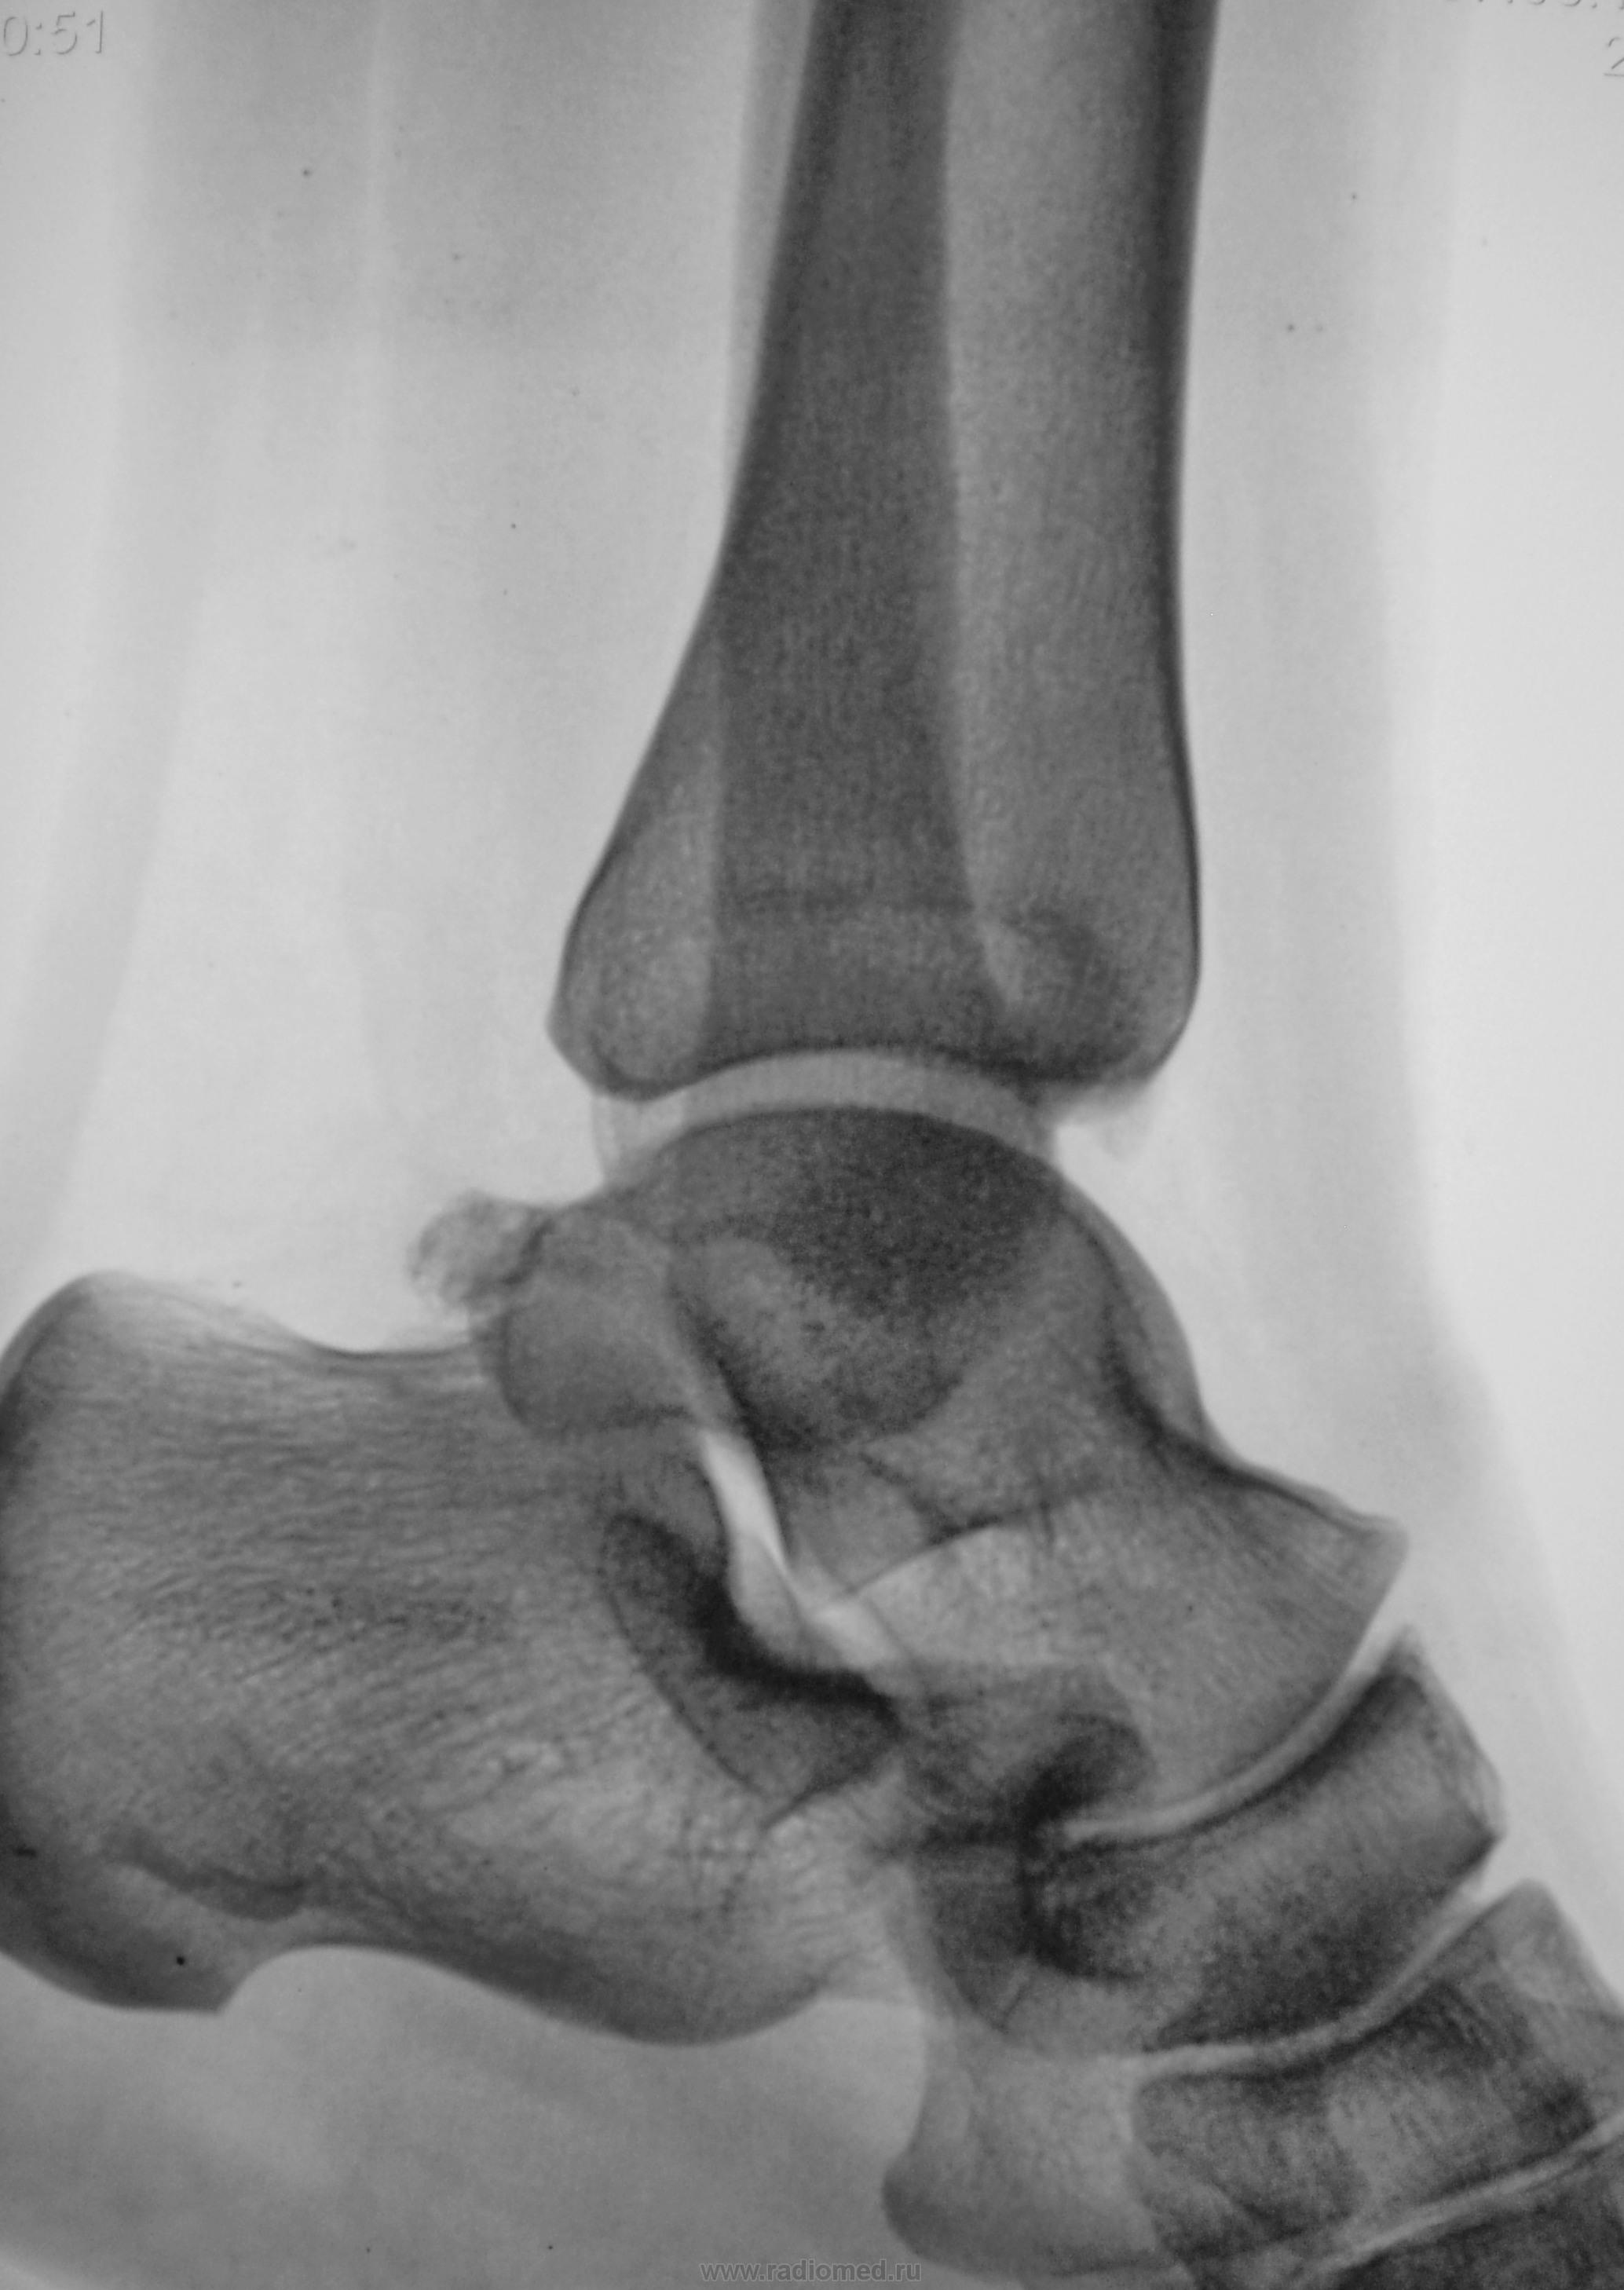

Травма.  Пациент направлен на рентгенографию голеностопного сустава.

Валентин Львович, Вы опять что-то каверзное припасли? Нужно сделать томографию - глядишь, все кости будут переломаны. Особливо прискіпливо(укр.) посмотреть на т.н. переднюю лодыжку.